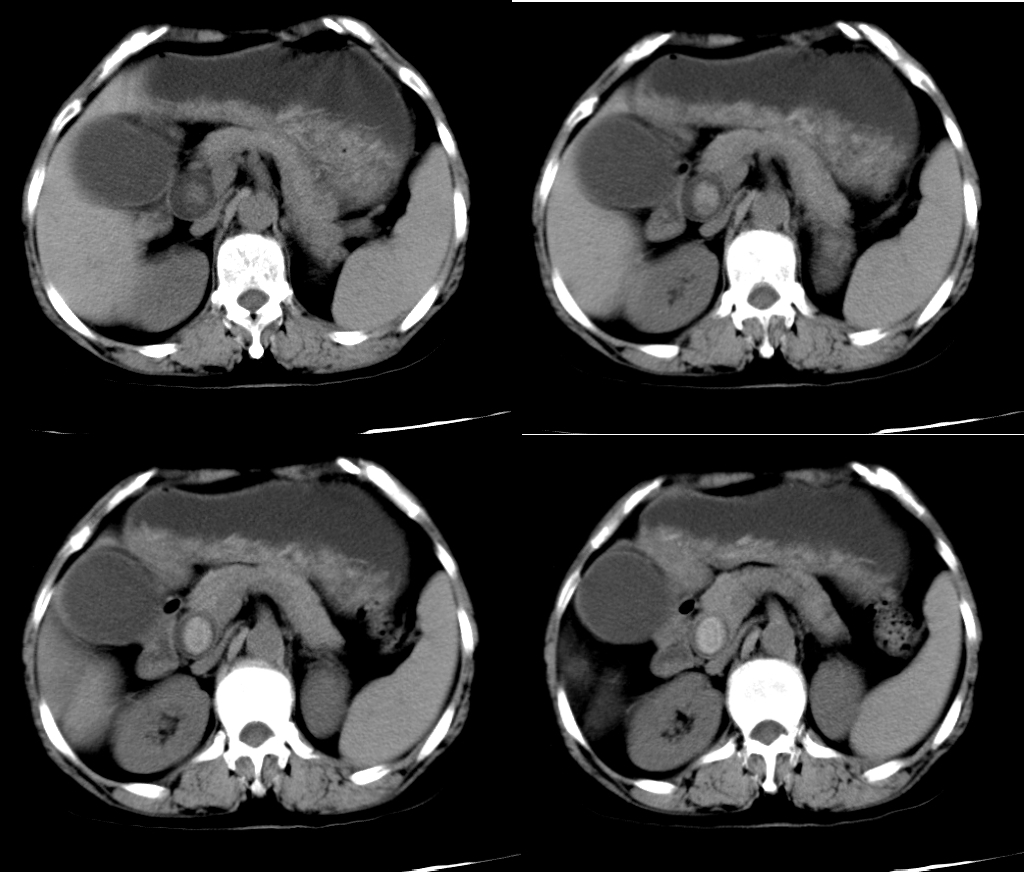

19、靶征

有多个名称,分别是:环靶征;双靶征;环征;双环征;三环征等。肝脓肿CT增强扫描的典型表现,因呈靶环状而得名。表现为肝内囊样低密度肿块病灶,边缘多数较模糊,脓肿周围往往出现不同密度的环形带(环征或靶征),增强扫描脓肿壁呈不同程度的环状强化,脓肿壁可为单环、双环或二环。

靶征是肝脓肿的典型征象,是脓肿形成期的表现。此期脓腔液化坏死彻底,脓肿壁可为单环,双环或三环,单环代表了脓肿壁,其周围水肿不明显;双环的内环代表脓肿壁,外环代表周围水肿带;三环表明脓肿壁由三层构成,外层(中环)为纤维肉芽组织,强化最明显,内层(内环)由炎性组织构成,强化不如外层纤维肉芽组织。肝脓肿靶征的出现代表着一定阶段病变的病理过程,为肝脓肿的特征性表现,对诊断很有价值。

大多数学者把肝脓肿的脓肿形成期CT表现认为是典型表现,表现为肝内囊样低密度肿块,病灶边缘多数较模糊,脓肿周围往往出现不同密度的环形带(环征或靶征),增强扫描脓肿壁呈不同程度的环状强化;少数患脓肿内出现气体,此时可肯定诊断。

CT平扫肝脓肿可发生于各肝叶,但以右叶多见,可单发或多发,大小不等。肝内低密度占位,CT值10~35Hu,边界多不清楚或部分模糊,脓肿周围壁较厚。病变组织坏死越完全,其密度越低、越均匀。如慢性肝脓肿,边缘清楚,CT值接近于水肿的密度,而且有时周围可见一圈高于脓腔低于正常肝组织的低密度水肿环,因而易于诊断。若脓肿内有气一液平面,表示液化比较完全,伴产气菌感染所致,通常被认为是诊断肝脓肿的特异性征象。

增强扫描使病灶内部结构、病灶边缘与正常肝组织的关系显示得更清楚。门脉期可显示肝脓肿较典型的CT征象,为典型三层病理改变增强后的CT表现,中心坏死区无强化,中间层为介于液化坏死区与正常肝组织之间的低密度带晕带环,外围层与正常组织分界模糊。慢性期由于脓肿周围形成血管丰富的结缔组织包膜,脓肿壁显著环形强化,其密度高于肝组织。环绕脓腔的为强化环,可以是单环、双环甚至三环。3个环相当于脓壁的3种病理结构:水肿、纤维肉芽组织和炎性坏死组织。如果3种结构存在则出现三环,否则出现双环或单环。

值得注意的是上述靶征并非肝脓肿特有,但环靶征对肝脓肿的诊断仍具有重要意义,因为肝癌、转移性肿瘤等出现环靶征的可能性很小。